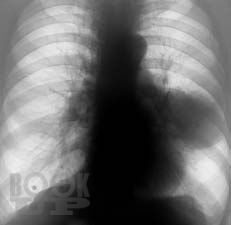

Клинико-рентгенологическая диагностика болезней органов дыхания

Основу данной книги составил архив клинико-рентгенологических наблюдений, собранный авторами в течение ряда лет. Авторы не стремились к подробному описанию клинико-рентгенологической диагностики многочисленных заболеваний бронхолёгочной системы. Материал излагается кратко, почти тезисно и отражает наиболее важные сведения об основной патологии органов дыхания. Цель книги — отражение вопросов клинической картины и рентгенодиагностики распространённых бронхолёгочных заболеваний в условиях муниципальных учреждений здравоохранения с позиции врача общей практики. Предназначено для терапевтов, семейных врачей, студентов медицинских вузов.